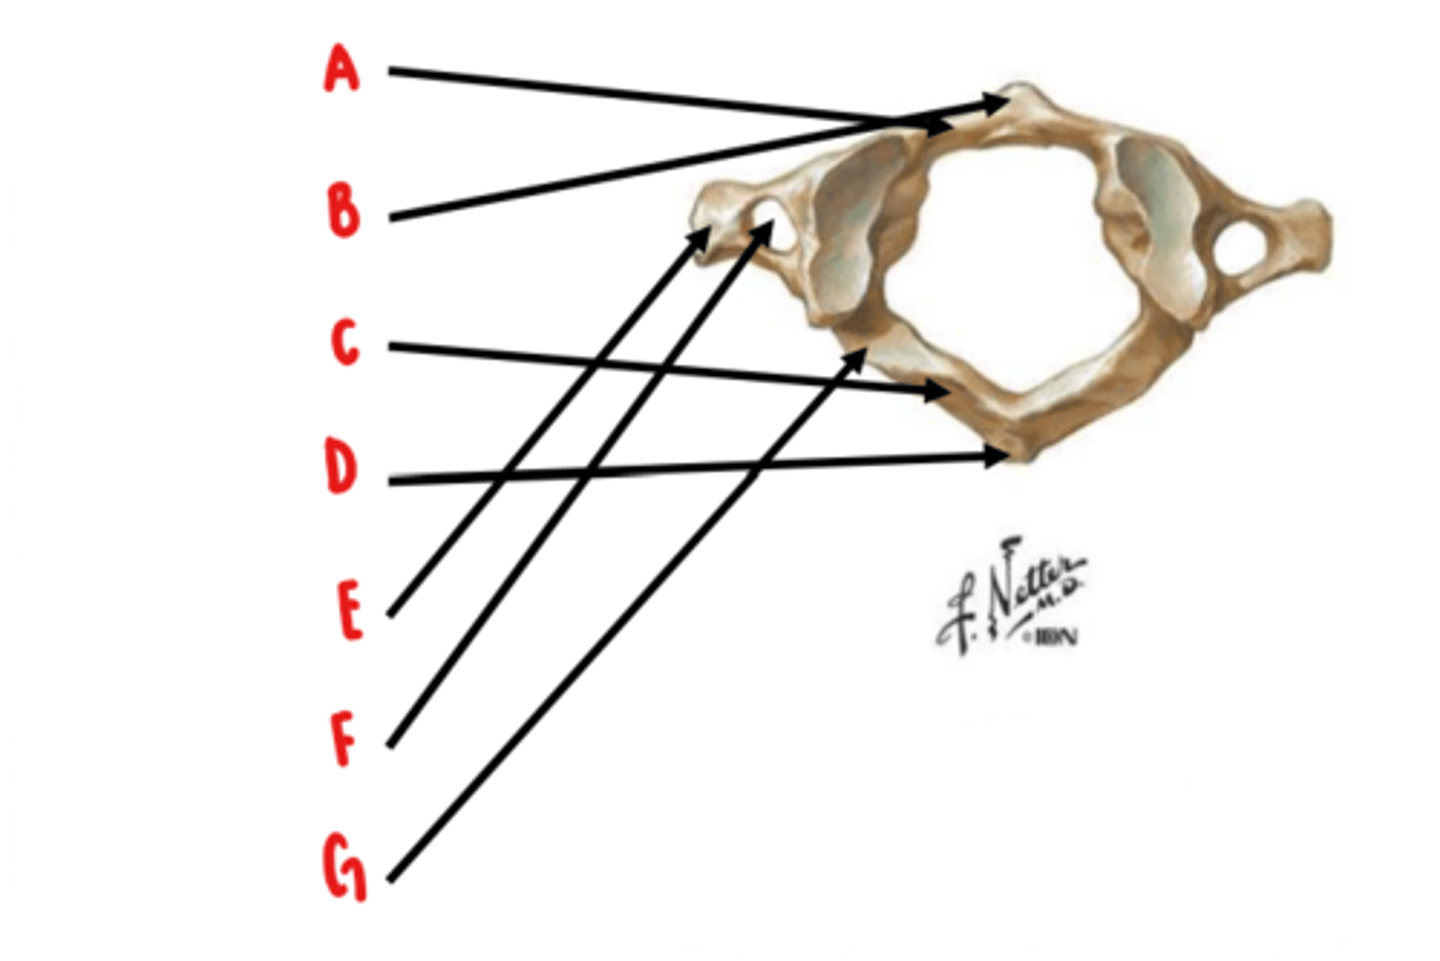

Atlas (C1)

What vertebrae is this?

anterior arch

Identify A

anterior tubercle

Identify B

posterior arch

Identify C

posterior tubercle

Identify D

transverse process

Identify E

transverse foramen

Identify F

groove for vertebral artery

Identify G

groove for vertebral artery in posterior arch

What is the easiest way to distinguish the superior surface of the atlas?